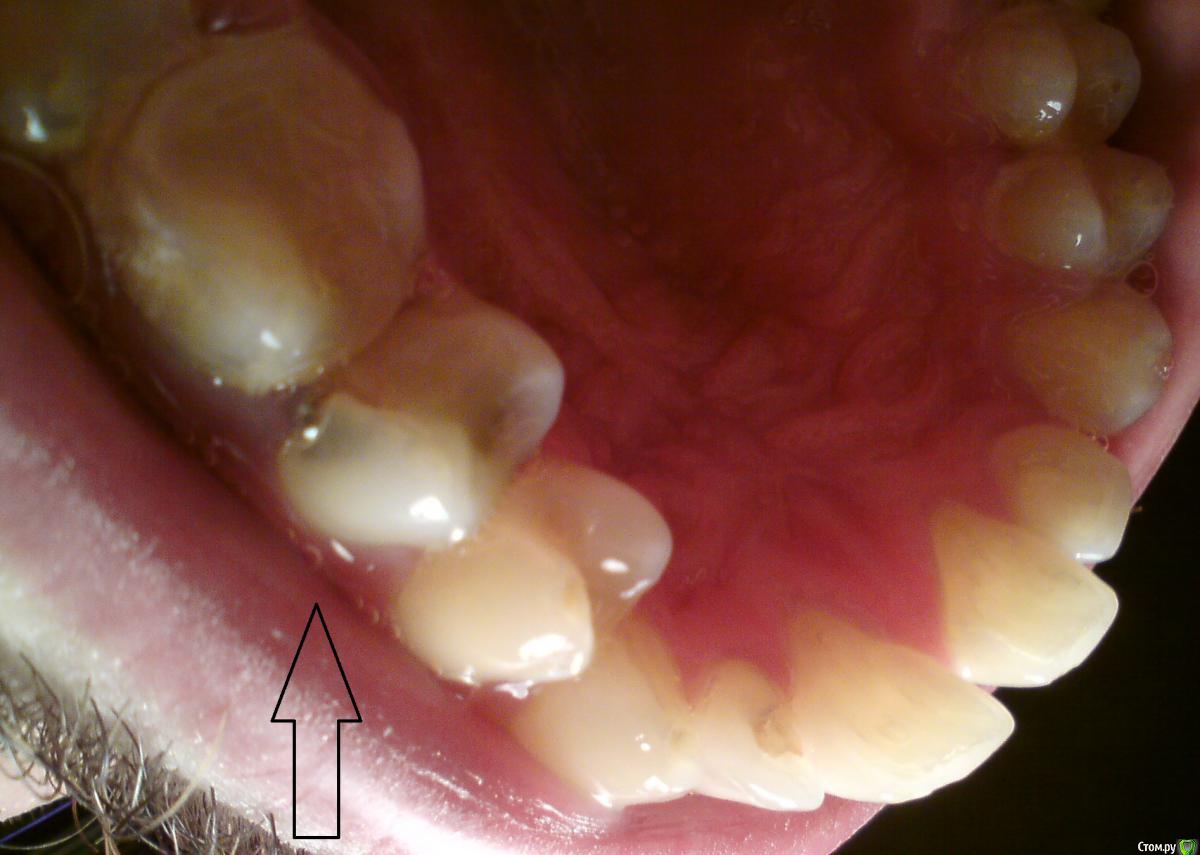

alex0814 Опубликовано 21 марта, 2015 Автор Поделиться Опубликовано 21 марта, 2015 Фото вот такое получилось. А шестерку перелечивать начинали уже - но там кариес под десну глубоко уходит. Видимо, придется удалять. Ссылка на комментарий

Гарриевич Опубликовано 21 марта, 2015 Поделиться Опубликовано 21 марта, 2015 пломба не из амальгамы а кариес есть зуб желательно закрыть накладкой (керамической) с перекрытием бугров Ссылка на комментарий

red_butler Опубликовано 21 марта, 2015 Поделиться Опубликовано 21 марта, 2015 кариес в 1.5 есть, к Кт гадалке не ходи Ссылка на комментарий

shishok Опубликовано 22 марта, 2015 Поделиться Опубликовано 22 марта, 2015 И на 22 кариес под пломбой. Ссылка на комментарий